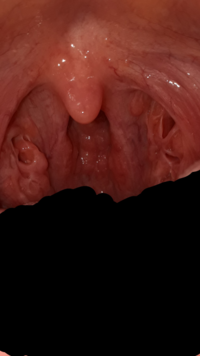

閲覧注意私のように扁桃腺凸凹している人いますか 膿栓 が溜ま yahoo 知恵袋